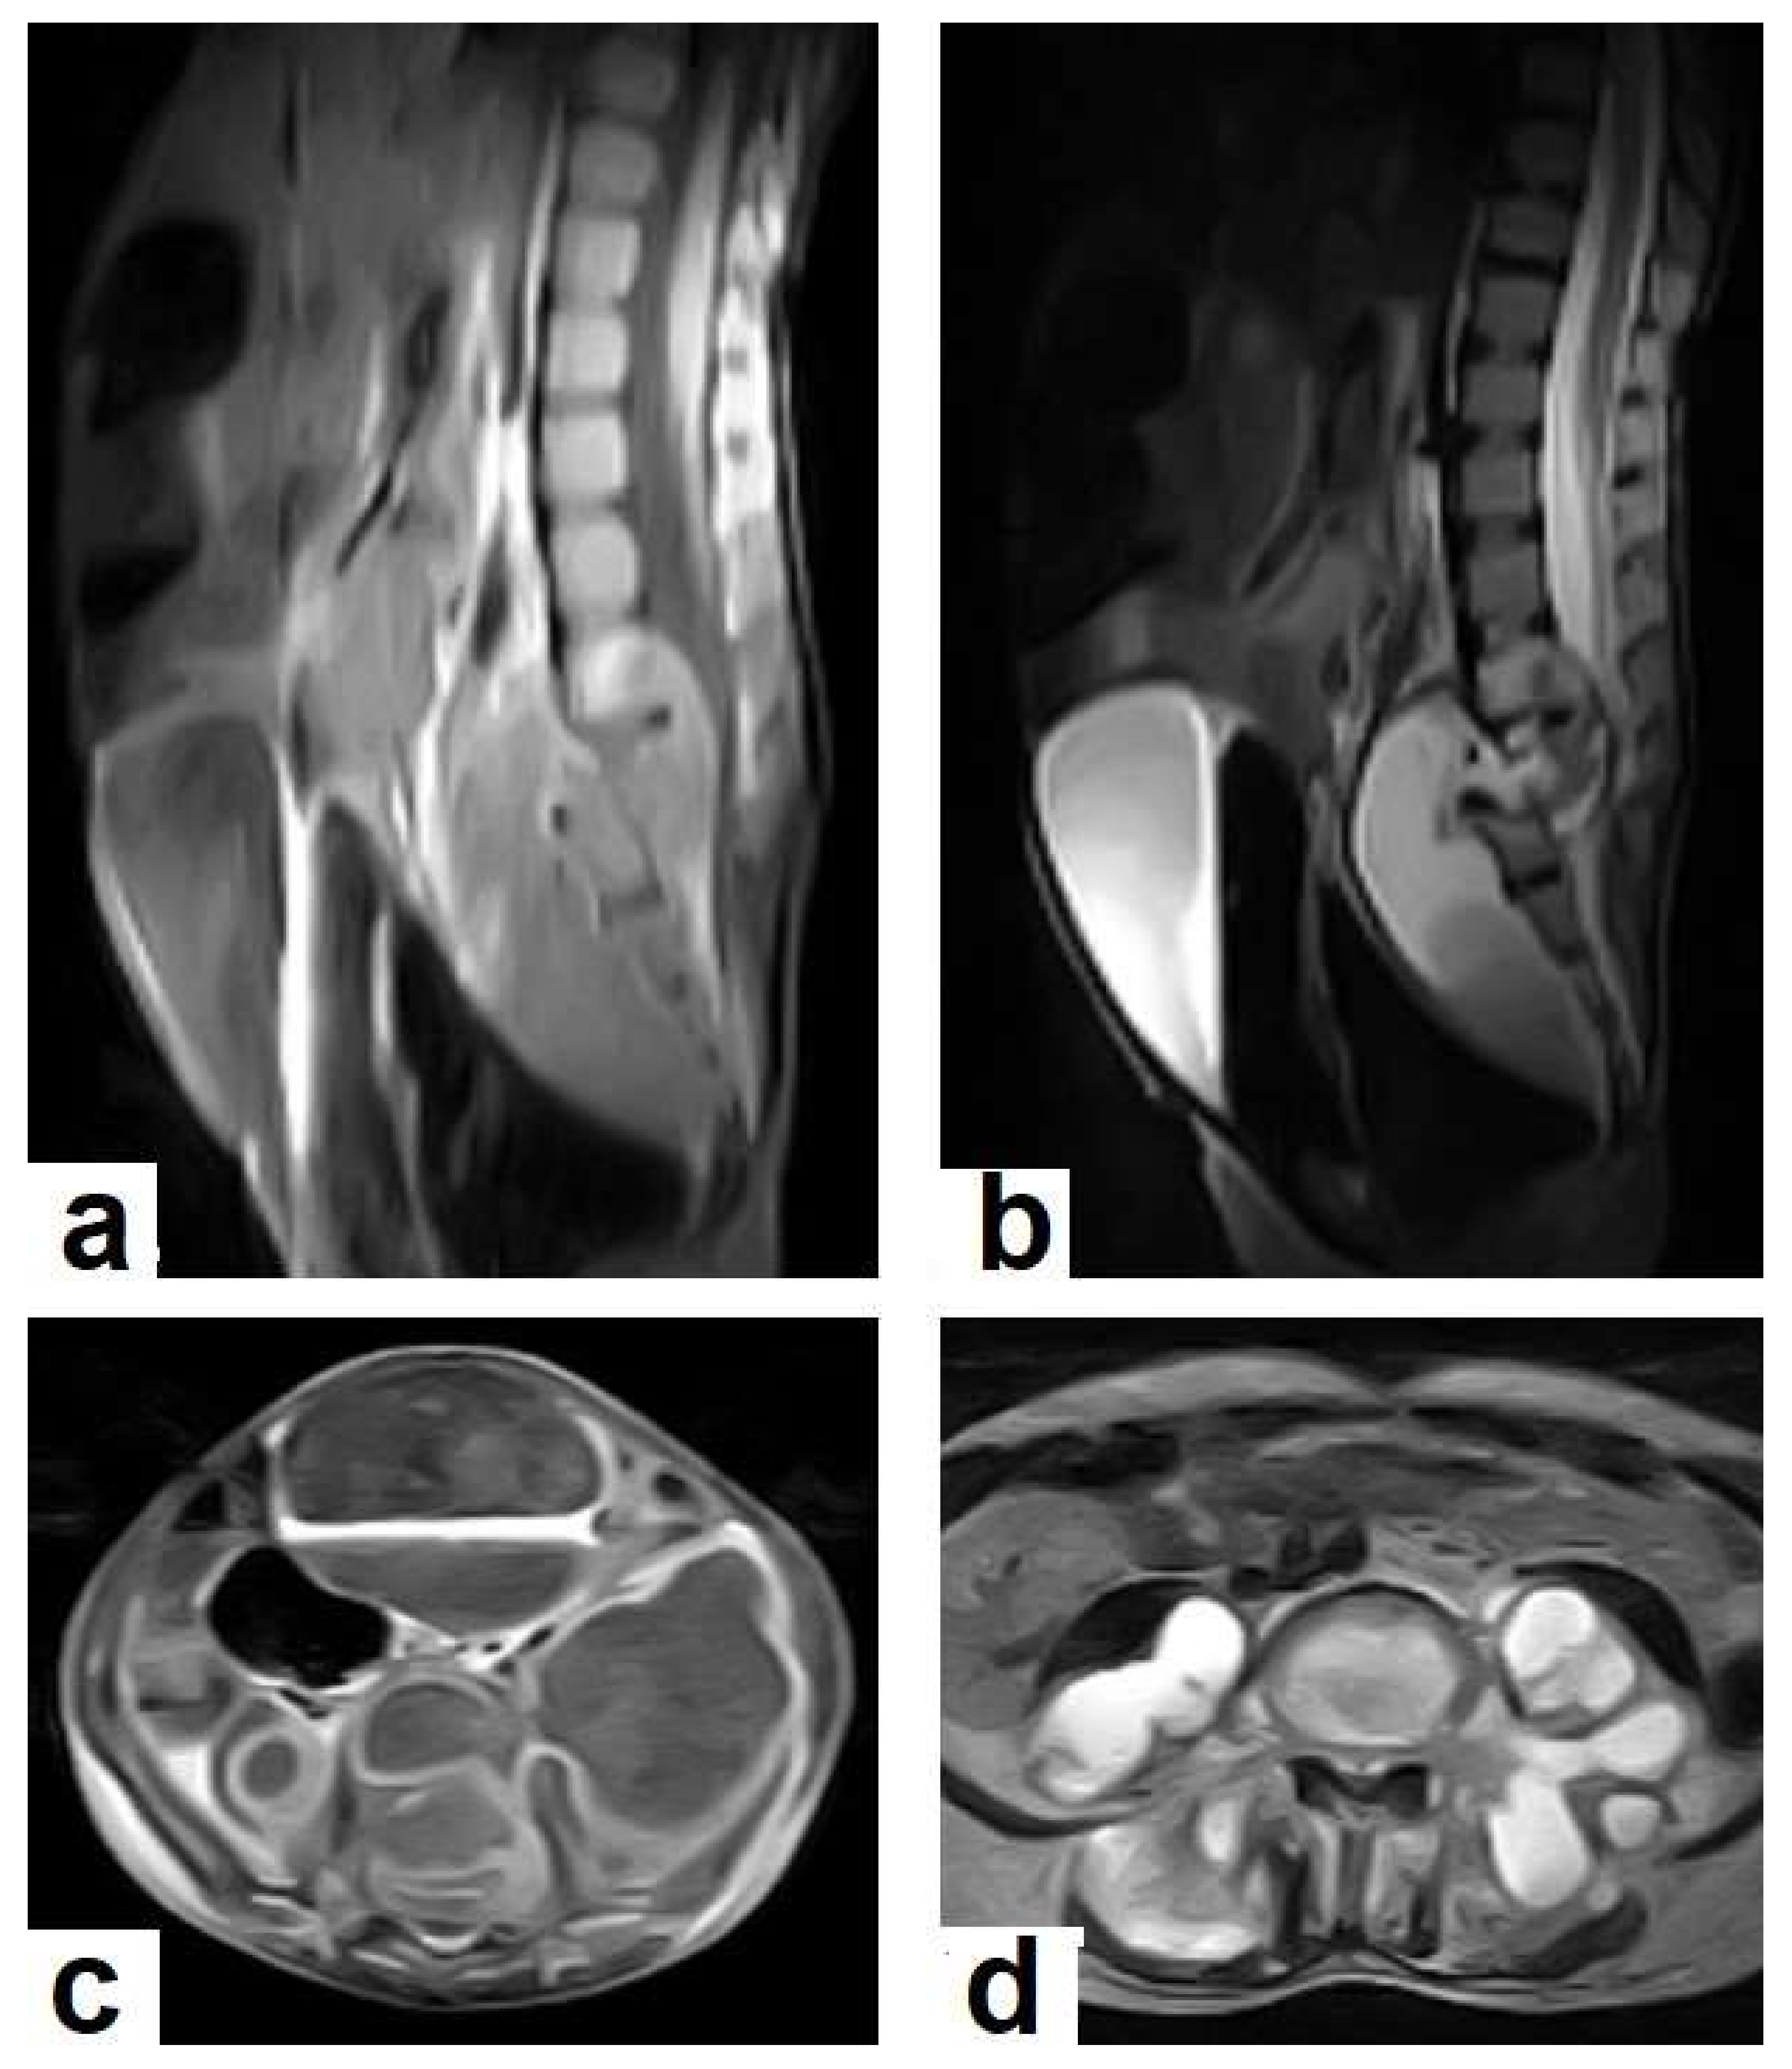

• Tuberculous spondylitis (Pott’s disease; Figure 18 and Figure 19) is a tuberculous infection of the spine that can affect any age and most commonly affects the lower thoracic and lumbar, followed by the cervical spine. It usually affects multiple contiguous vertebrae with paraspinal extension, causing subdural or epidural abscess formation and resultant spinal cord compression, which is a leading cause of paraplegia [27]. CT demonstrates the extent of bone involvement, while MRI demonstrates spinal-cord and soft-tissue involvement. Tuberculous spondylitis appears as a well-defined paraspinal abnormal signal intensity, as a thin wall abscess, or a combination of intraosseous and soft tissue abscesses. The spread of infection is sub-ligamentous beneath the anterior longitudinal ligament involving multiple vertebrae with high signal intensity on T2WIs. Pott’s disease is a difficult differential diagnosis with a spinal pyogenic infection. MRI demonstrate have 100% sensitivity, 80% specificity, and 90% accuracy in differentiating tuberculous from pyogenic spinal infection [34].

Figure 19. Pott’s disease in a 6-year-old female patient. Selected images of lumbosacral MRI. Sagittal (a) T1-weighted images and (b) T2-weighted images show that destructive lesion involves the T4/T5 disc and vertebrae, with extensive pre-vertebral loculated fluid collection. Selected axial images of MRI (c) T1-weighted image with gadolinium, and (d) T2-weighted image shows bilateral paravertebral loculated fluid collections involved in bilateral psoas; paravertebral muscles appear to have low-signal-intensity contents on T1-WIs with marginal enhancement after contrast administration and high-signal-intensity contents on T2-WIs (arrows). The picture is typical of Pott’s disease with bilateral psoas and paravertebral abscesses.